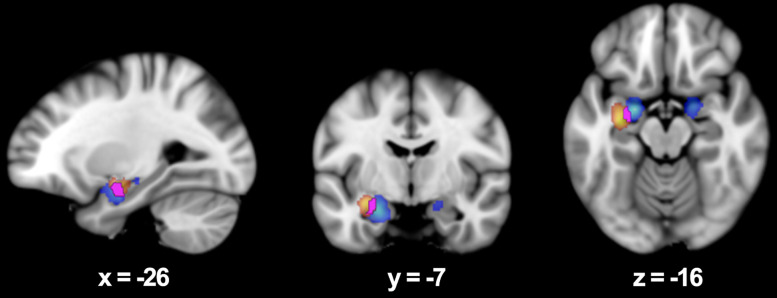

Methods: A meta-analysis was conducted using peer-reviewed, event-related fMRI studies. The Activation Likelihood Estimation (ALE) method was applied via GingerALE software to compare brain activations associated with the encoding of affective visual stimuli presented as either words or photographs. Three contrasts were assessed: pictures > neutral + control, words > neutral + control, and overlap between both.

Results: Picture stimuli elicited bilateral activation in the medial parahippocampus, while word stimuli produced left-lateralized activation in the lateral parahippocampus. The overlap analysis identified a shared region in the parahippocampal amygdala. All three contrasts revealed significant activations in key medial temporal lobe (MTL) regions involved in emotional memory, including the hippocampus and amygdala.

Conclusions: Both stimulus types engaged medial temporal networks specialized in emotional memory encoding. Word stimuli selectively activated regions lateralized to the left hemisphere, whereas picture stimuli produced bilateral activation with a leftward bias. This study provides the first meta-analytic evidence of a medial-lateral differentiation in the parahippocampal gyrus based on emotional stimulus type.